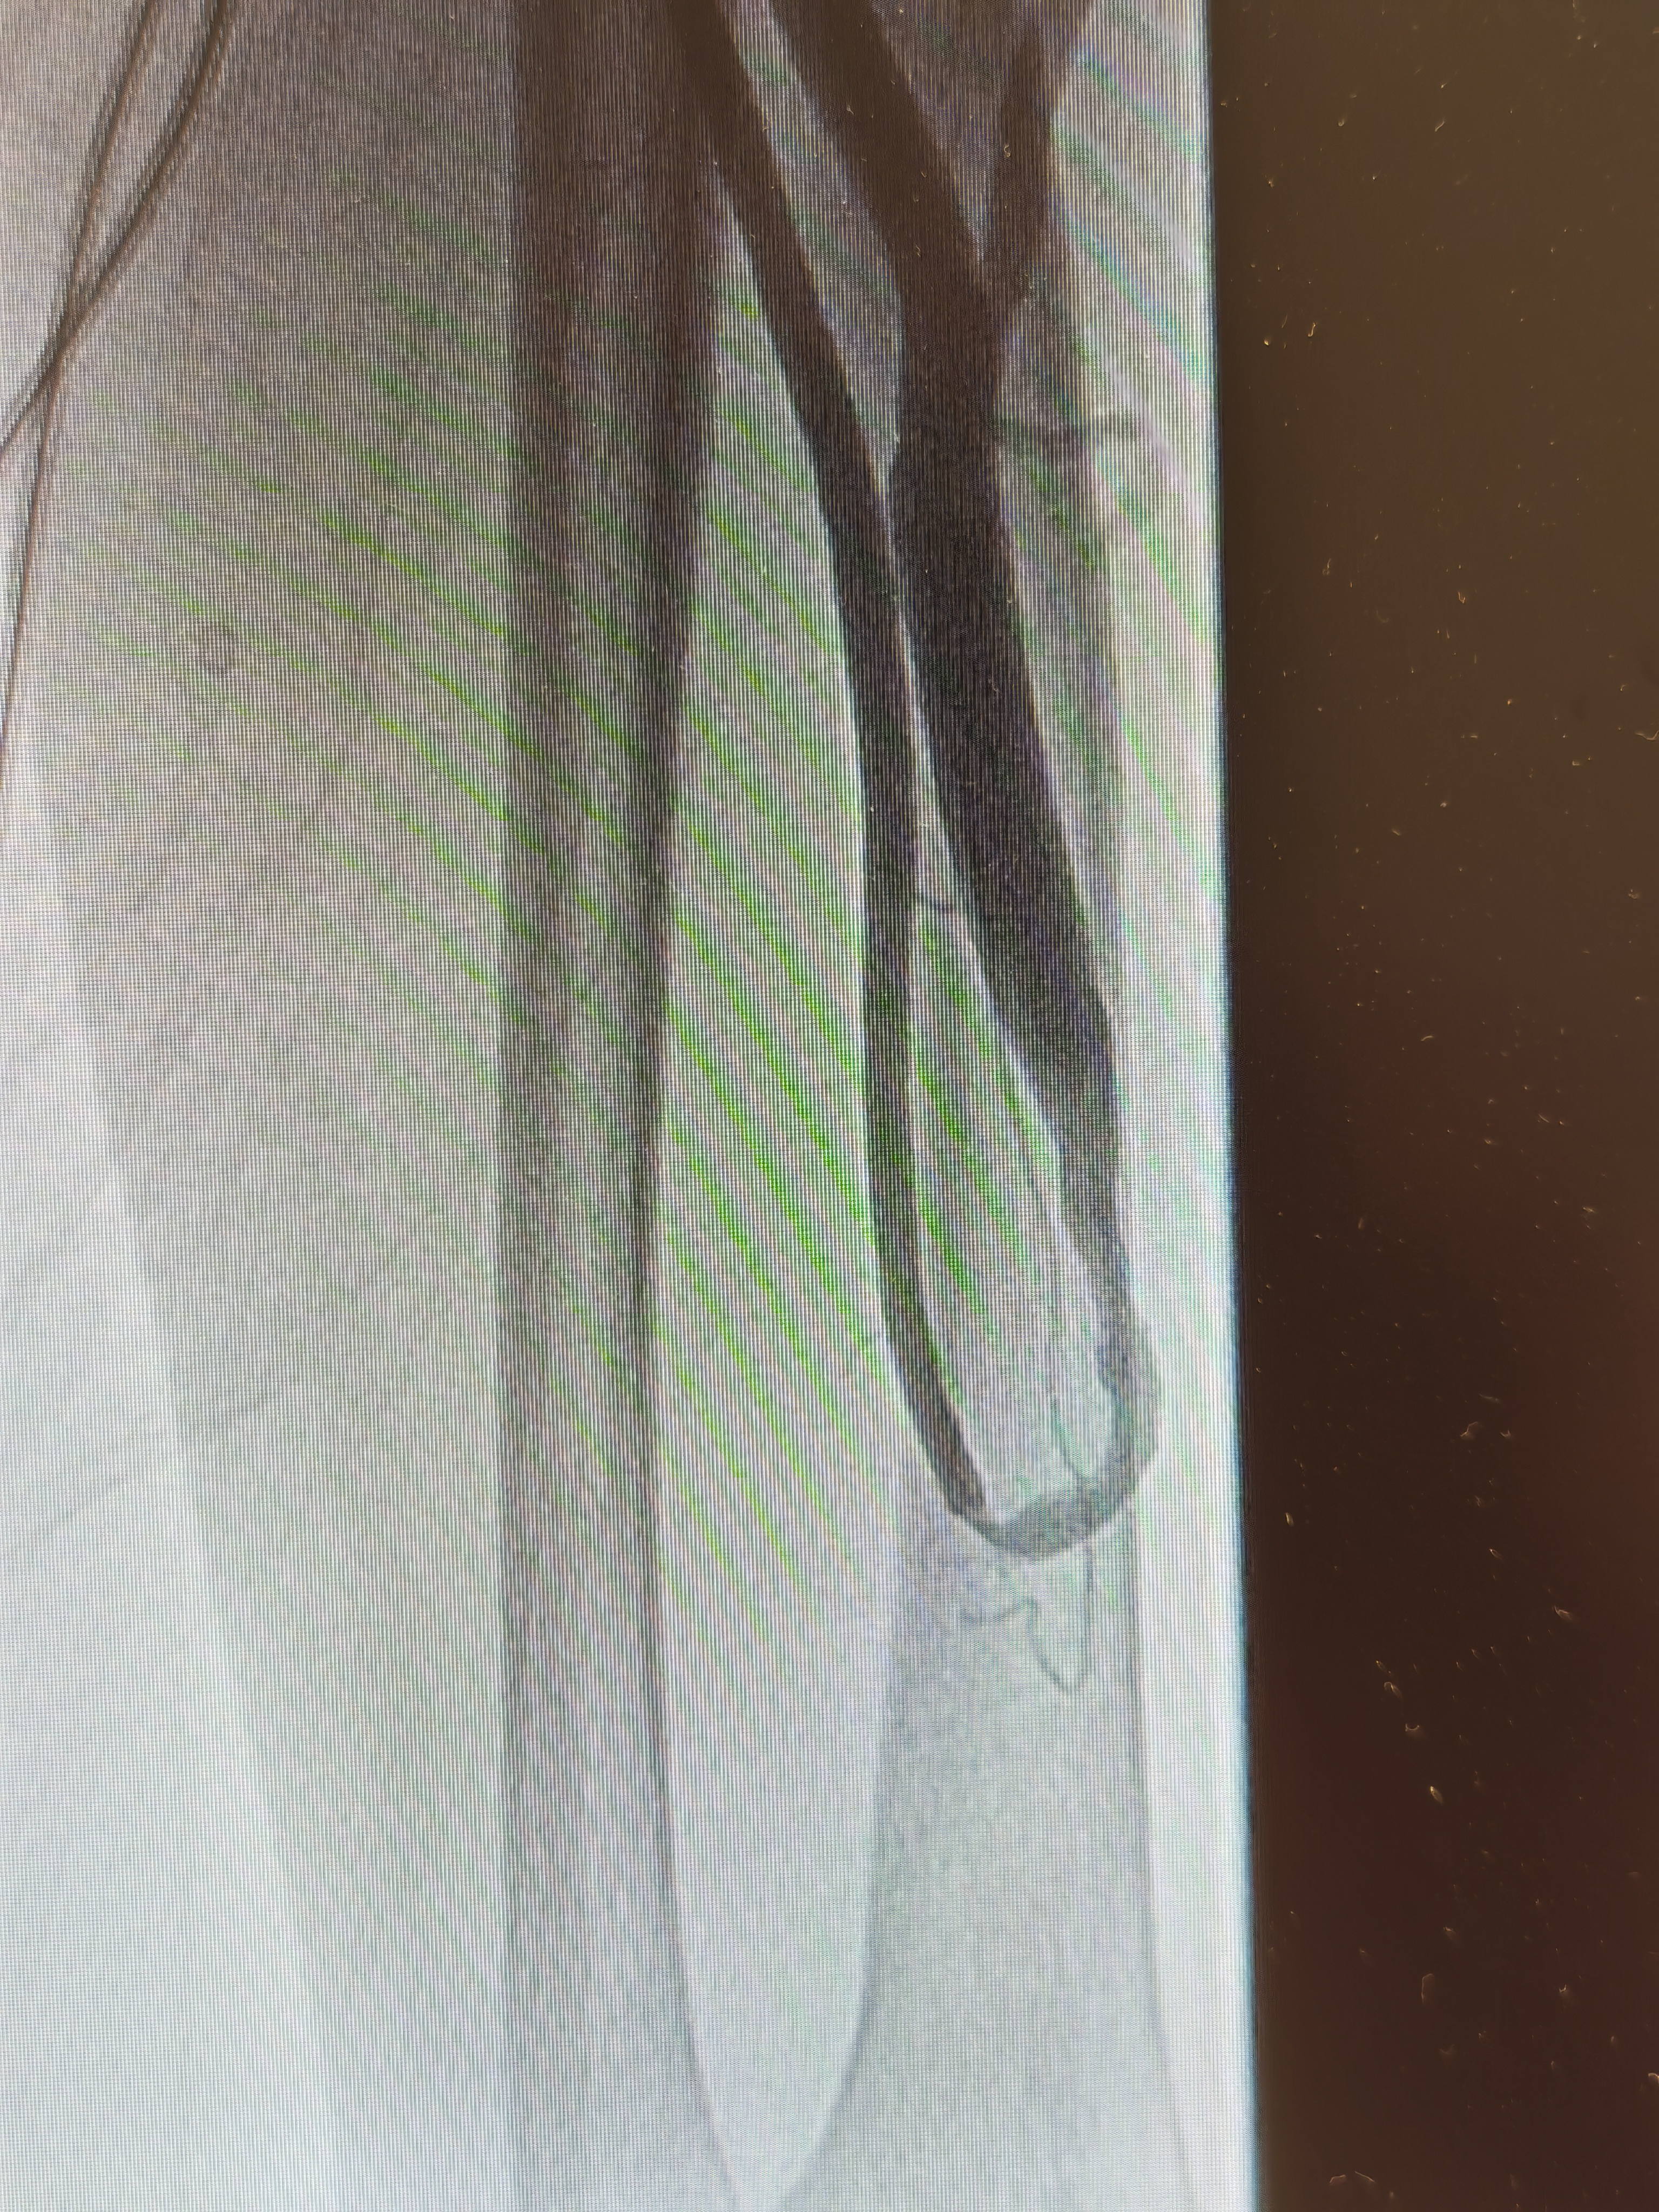

患者入院后,医院立即启动肾病血透通路 MDT 多学科会诊。四川泰康医院副院长、血管介入博士、血管通路专家郭伟昌牵头,为患者量身制定个体化手术方案。在充分术前准备下,郭伟昌副院长带领肾内科团队,为患者实施经肱动脉入路 DSA 下动静脉内瘘造影 + 球囊扩张 + 腔内溶栓术。术中造影显示,患者内瘘瘘口狭窄约 80% 并伴血栓形成。郭伟昌副院长精准操作,以 5 mm 高压球囊扩张病变,并予以尿激酶溶栓。术后复查造影显示,狭窄段完全开通,血流通畅。术后第二天,患者即可使用内瘘顺利透析,彩超复查血流量恢复至理想水平。